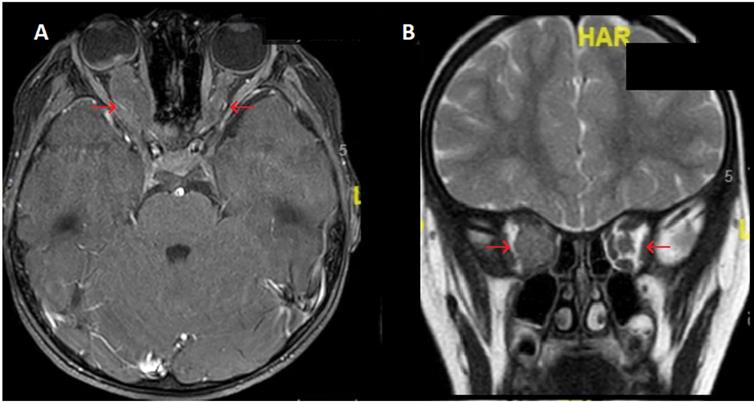

Ophthalmic relapse was the 1st relapse for 18 children. In the 2 other patients, ophthalmic relapse occurred after a BM relapse and a CNS relapse. The median age at ophthalmic relapse was 9.9 years (range 1.8 to 18.6 years). Relapse was diagnosed with a median delay of 24.7 months (range, 5.5 to 129.4 months) after the initial ALL diagnosis, occurring earlier in patients with T-ALL (9.9 months vs 33.1 months for patients with BCP-ALL; p value = 0.06). Eleven children (55%) relapsed early (< 30 months after initial diagnosis). Characteristics of ophthalmic relapses are described in Table 2. The eye segment involvement was anterior for 6 children. Ophthalmic symptoms appeared progressively (more than 15 days) for 8 children, whereas the remaining 12 (60%) had acute symptoms. Patients displayed variable clinical manifestations: the most frequent symptoms being reduced visual acuity (n = 12) and ocular pain (n = 5). Six patients had a bilateral ophthalmic involvement (30%). Nine of the 16 patients with available fundus images (56%) had papilledema related to blastic tumor invasion (Fig. 1), 1 (6%) had exudative retinal detachment (sign of choroidal damage). None of our patients displayed signs of leukemic retinopathy, specifically no extensive ocular hemorrhage which is a sign of bone marrow failure. At ophthalmic relapse, 15 children (75%) had a concomitant involvement of the CNS. Among our 20 patients, 18 had undergone brain imaging. The images of 8 of them showed signs of retro orbital invasion: contrast of the optic nerves n = 5; contrast of meningeal n = 1; intracerebral process n = 2 (Fig. 2). Among the remaining 10 patients, 5 had an abnormal ocular contrast on cerebral magnetic resonance imaging indicative of leukemia cell invasion, without sign of retro orbital invasion (lens n = 1, retinal n = 1, conjunctival n= 1, orbital wall n = 2) and 5 patients had a normal imaging. Eleven patients (55%) had a combined BM involvement (cytological n = 7; MRD > 10-2 n = 2; MRD < 10-2 n = 2). Only 1 patient had an isolated ophthalmic relapse. This patient relapsed with an isolated peri-macular lesion 7 months after HSCT, yet displayed a normal cerebral MRI, cerebrospinal fluid (CSF) analysis and negative BM MRD. Despite the lack of documentation on posterior chamber puncture, he was treated with HD-MTX combined with protontherapy before CNS relapse 10 months later. Only 6 patients had cytological confirmation of ocular involvement (4 anterior chamber paracentesis and 2 palpebral biopsy).

Figure 2

Brain magnetic resonance imaging (MRI) of BCP-ALL ophthalmic relapse for a child with massive infiltration of the right optic nerve. Images show a major circumferential thickening of the homogeneous right optic nerve with little contrast with lesser involvement of the left optic nerve. A. Axial THRIVE sequences after gadolinium injection B. Coronal T2. Legend: ALL: acute lymphoblastic leukemia